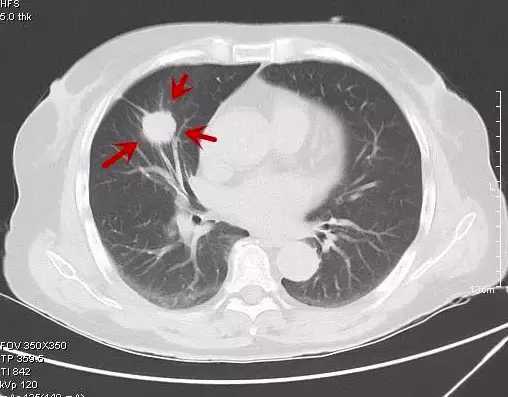

第五类:浸润性腺癌(IAC)(实性结节)

意义:典型肺癌,有转移的能力,且能力大。

典型影像表现:结节分叶状、有毛刺、有胸膜凹陷、有血管集束征等典型恶性征象(不一定同时具备)。

手术与否:只要没有远处转移,宜立即手术!首选肺叶切除及淋巴结清扫,妥协性时也可肺段切除并清扫淋巴结。